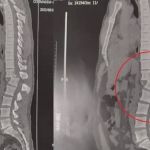

Homem atingido por aparelho de musculação em academia volta a sentir as pernas

'Já estou sentindo na lateral [parte externa] das coxas', disse em entrevista ao g1; médicos afirmam que o motorista tem apenas 1% de chance de voltar a andar

Homem atingido por aparelho de musculação passou por cirurgia e tem 1% de chance de voltar a andar

De acordo com o hospital, o quadro de saúde é estável; procedimento ocorreu em quatro horas